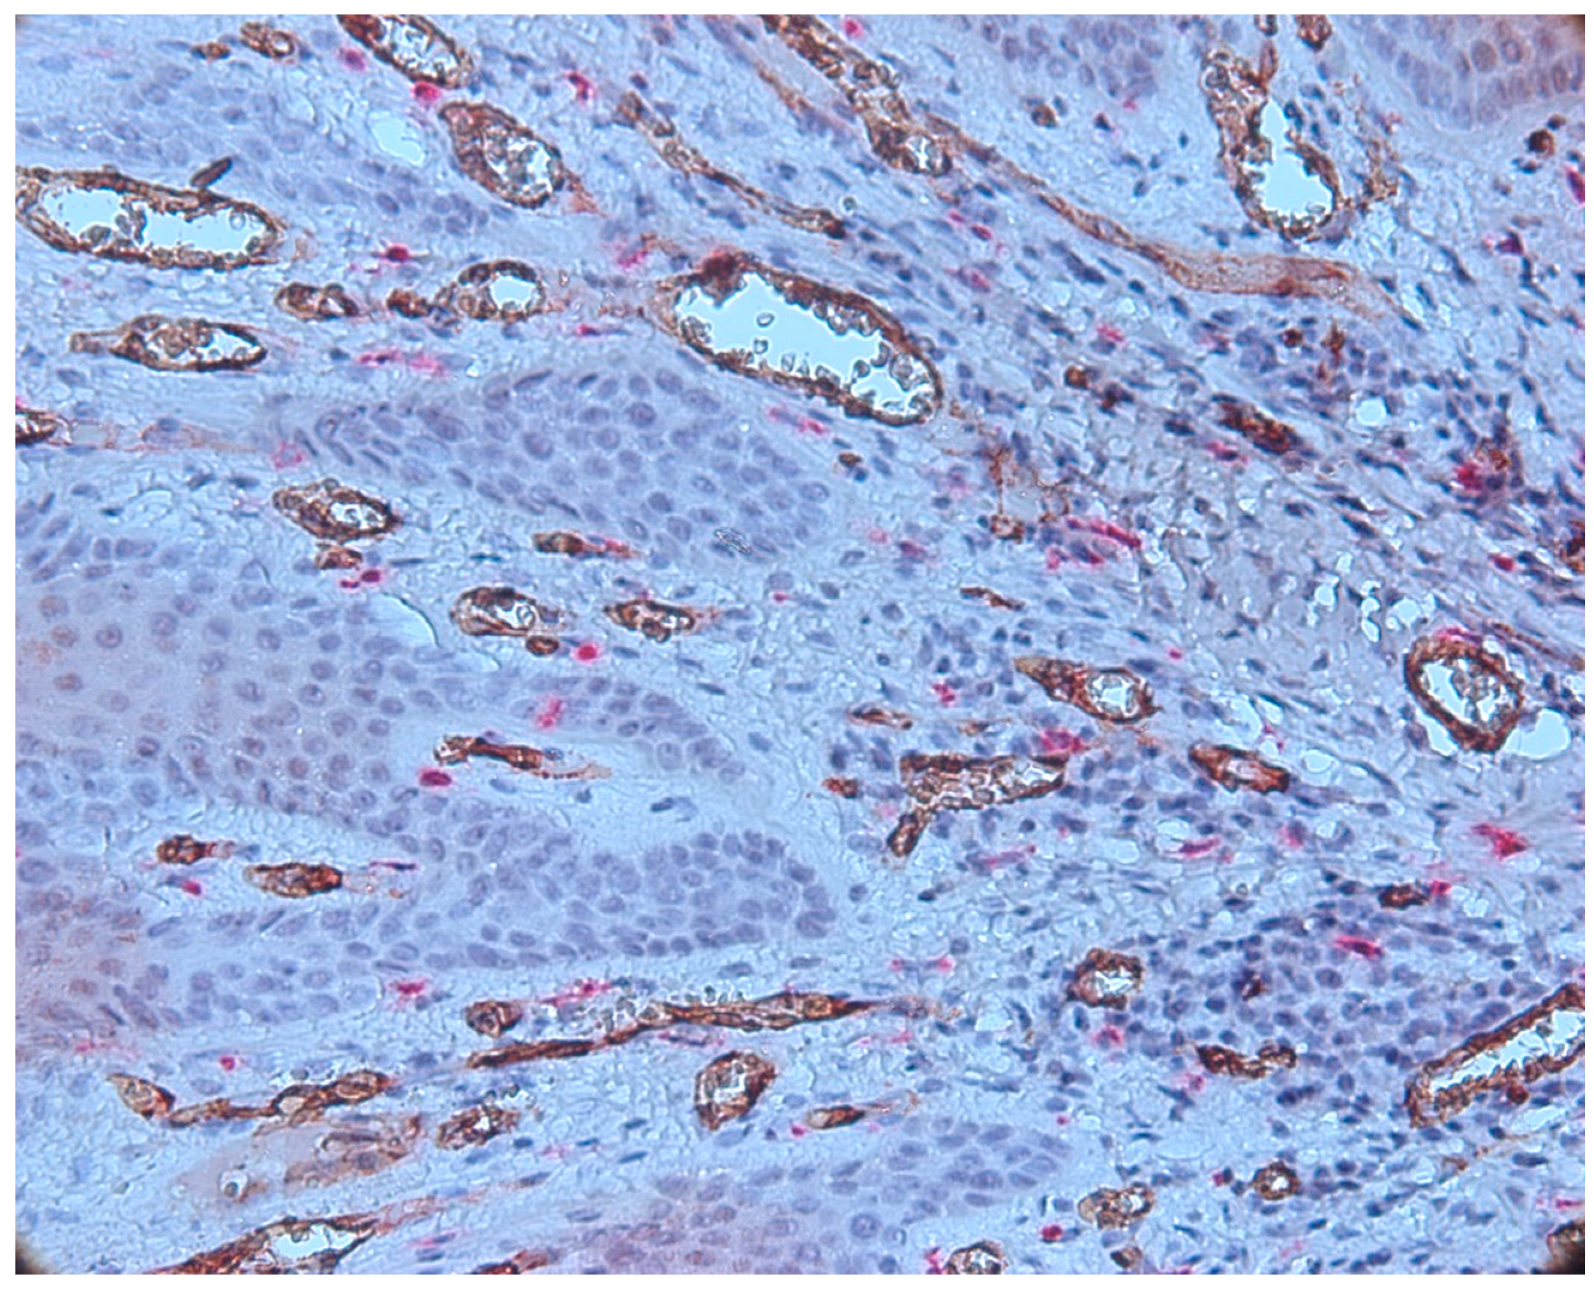

3.3. Aspects of Microvessels

| Intraepithelial Vessels | Subepithelial Vessels | Connective Tissue Vessels |

|---|---|---|

| Mean (SD): 1.4 (2.2) | Mean (SD): 7.8 (6.5) | Mean (SD): 14.9 (3.9) |

| Range: 0.0–9.7 | Range: 0.0–20.3 | Range: 0.0–23.2 |